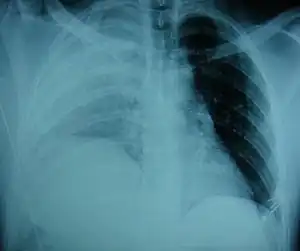

An X-ray showing a raised diaphragm on the right due to a rupture of the diaphragm on that side.[1] | |